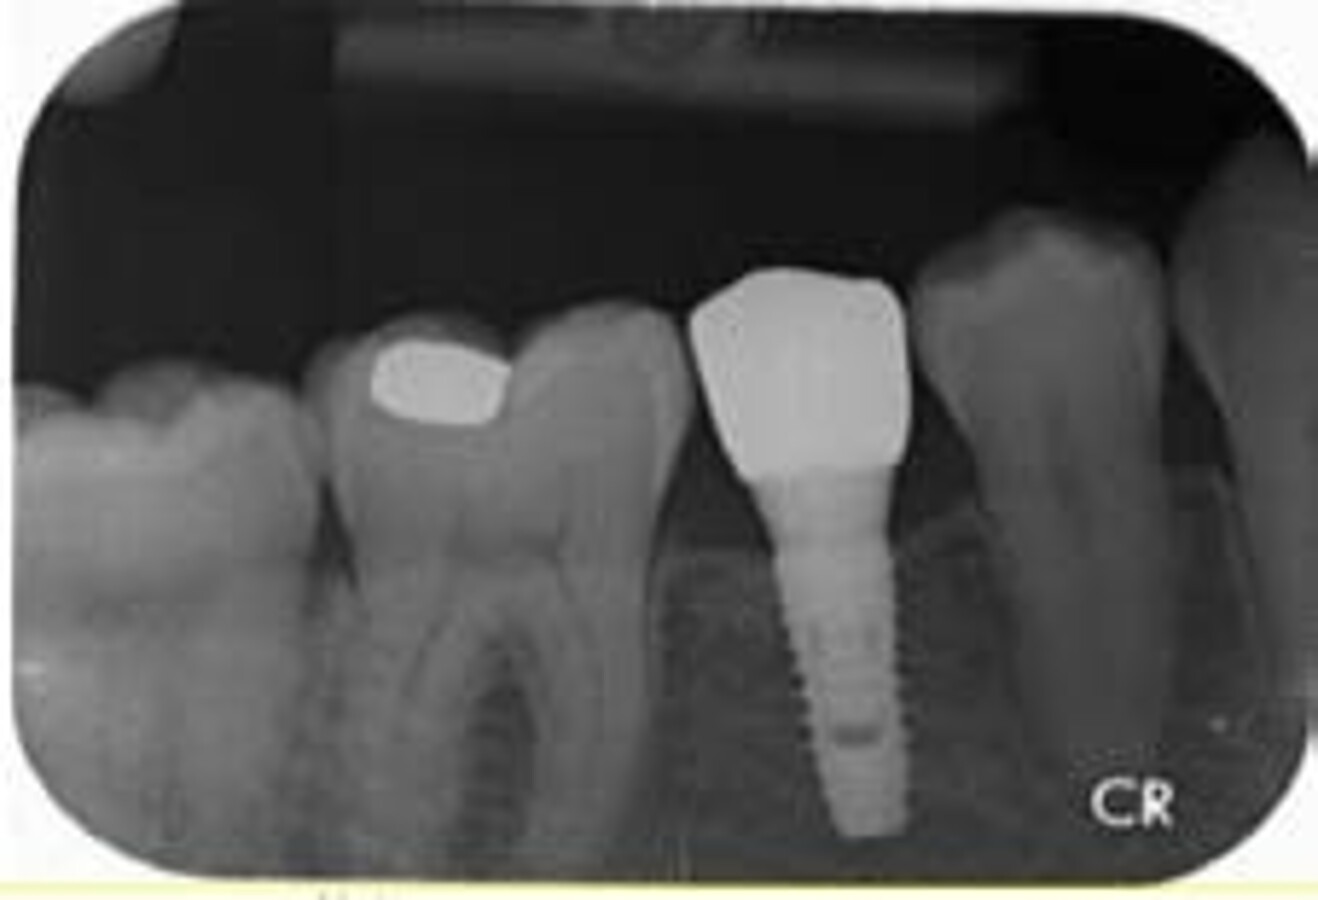

Fig. 4: Immediate post-operative IOPA of implant in site 35